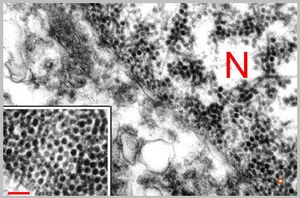

F,50y. | progressive multifocal leukoencephalopathy- viral particles in a glial cell

F,50y. | progressive multifocal leukoencephalopathy- viral particles in a glial cell

F,50y. | progressive multifocal leukoencephalopathy- viral particles in a glial cell